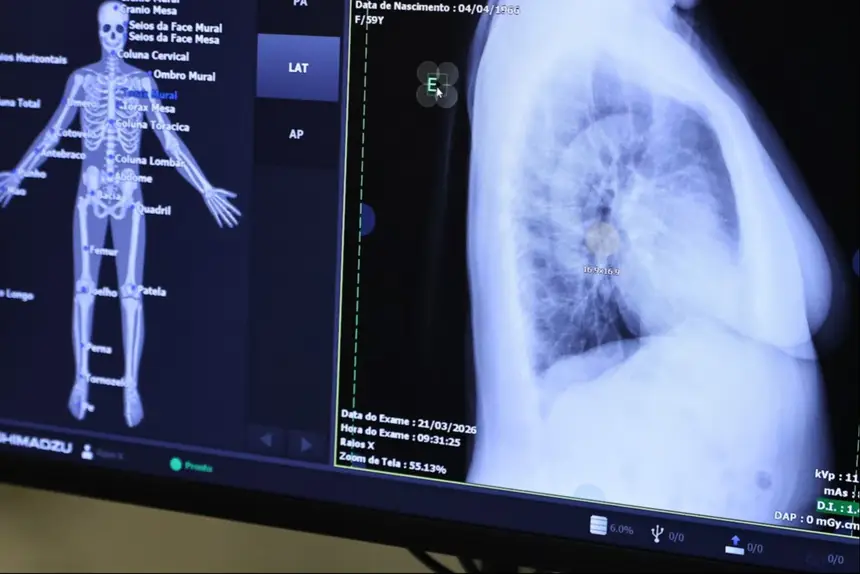

O Governo do Estado participou da edição do Dia E – Ebserh em Ação, focada na saúde da mulher, com a realização de quase mil atendimentos e a entrega de um moderno parque tecnológico de imagem para atendimentos no Hospital Universitário da Universidade Federal do Amapá (HU/Unifap).

O Centro Tecnológico é composto por aparelhos de ressonância magnética, tomógrafo computadorizado, equipamento de mamografia, raio X telecomandado e densitometria óssea.

Os equipamentos foram adquiridos por meio de contratação e fazem parte do plano de qualificação de exames por imagem.